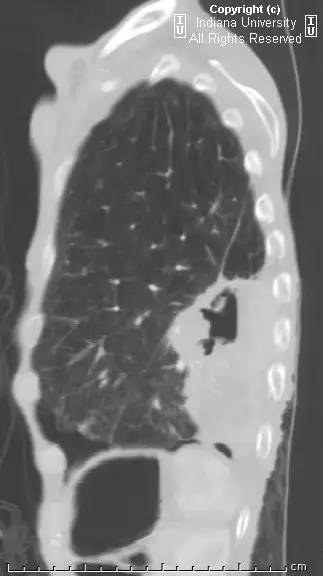

胸片示肺内高度膨胀性病变,膈肌扁平。左后胸部可见较大卵圆形不透亮区并液平面。CT示左肺下叶近后胸壁较大厚壁肿块并部分空洞形成,实性部分不均质强化。右肺下叶可见分叶状结节。左前下少量气胸。

【诊断】鳞状细胞肺癌并后部阻塞性肺炎